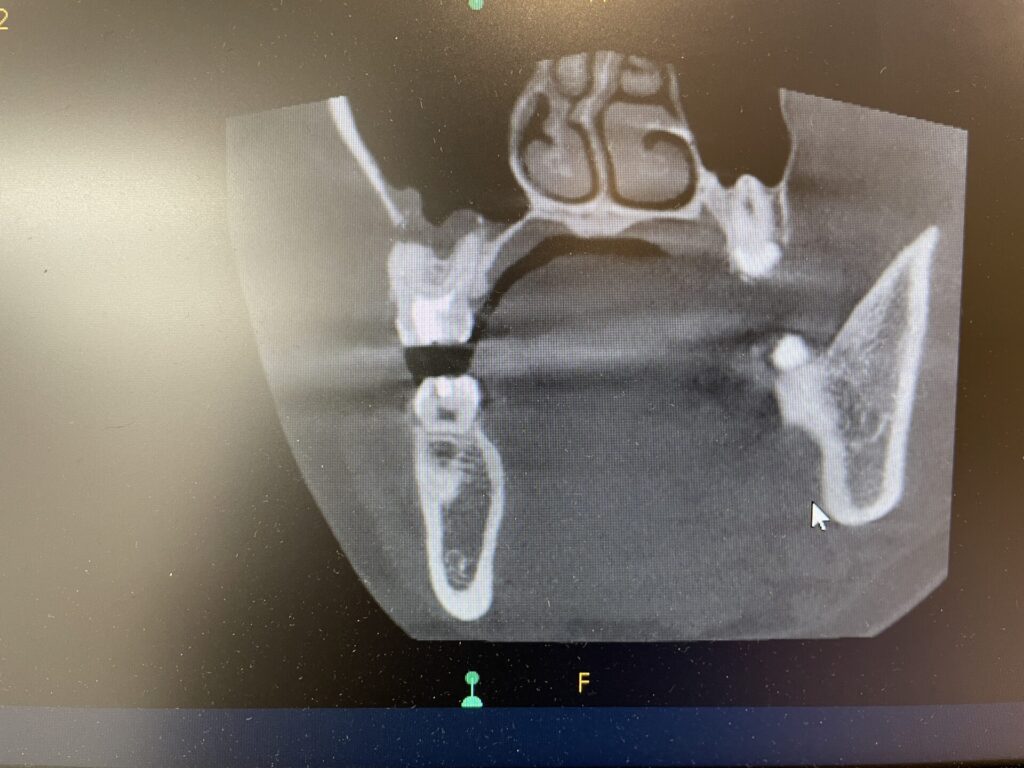

上の右奥の歯ぐきにニキビ様のものが出来ています。これもなかなか治らないとのことでした。デンタルレントゲンやCT検査の結果、大臼歯の根3本とも先端に膿がある状態でした。根管治療も中途半端な状態で仮の蓋が詰めてあるだけでした。

初診時のデンタルレントゲン・CT画像

ラバーダム防湿を行い、マイクリスコープ下での治療です。近心の根には2つの根管があります。この第2根管は裸眼の治療では高頻度で見落とされる傾向にあります。CTを事前に撮影しておくことで複雑な歯の神経の道を事前に把握することは非常に重要です。

第2根管までしっかりと根管充填が出来ていることがわかります。また上顎洞粘膜の腫れも軽減していることがわかります。